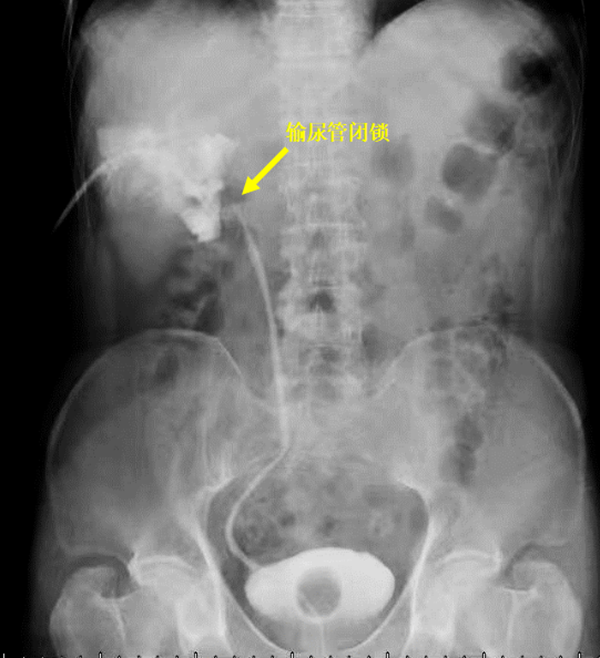

术后复查,肾积水并没有好转,于是,李先生在当地医院进行了“肾造瘘”,造瘘后造影提示肾门部输尿管狭窄完全闭锁。难道一辈子只能靠“造瘘”生活?李先生不甘心,在得知上海仁济医院尿路修复团队在输尿管狭窄修复领域有许多类似成功治愈的病例后,经病友推荐,李先生随即慕名来到仁济医院进行治疗。

“输尿管是连接肾脏和膀胱的尿路通道,当各种原因所导致的输尿管管腔较正常变窄时就会堵住尿液的输送,造成上尿路的梗阻、肾积水和肾功能损害,使输尿管引流不畅,管腔变窄的情况,都叫输尿管狭窄。”据仁济医院泌尿科尿路修复亚专业主治医生吕向国介绍,由于导致输尿管狭窄的原因很多,对其治疗同样也受多种因素的影响,在临床上,治疗方案也缺乏一定的标准。因此,对多种因素的综合评估,开展对患者的个体化治疗才是攻克这一疾病的关键。